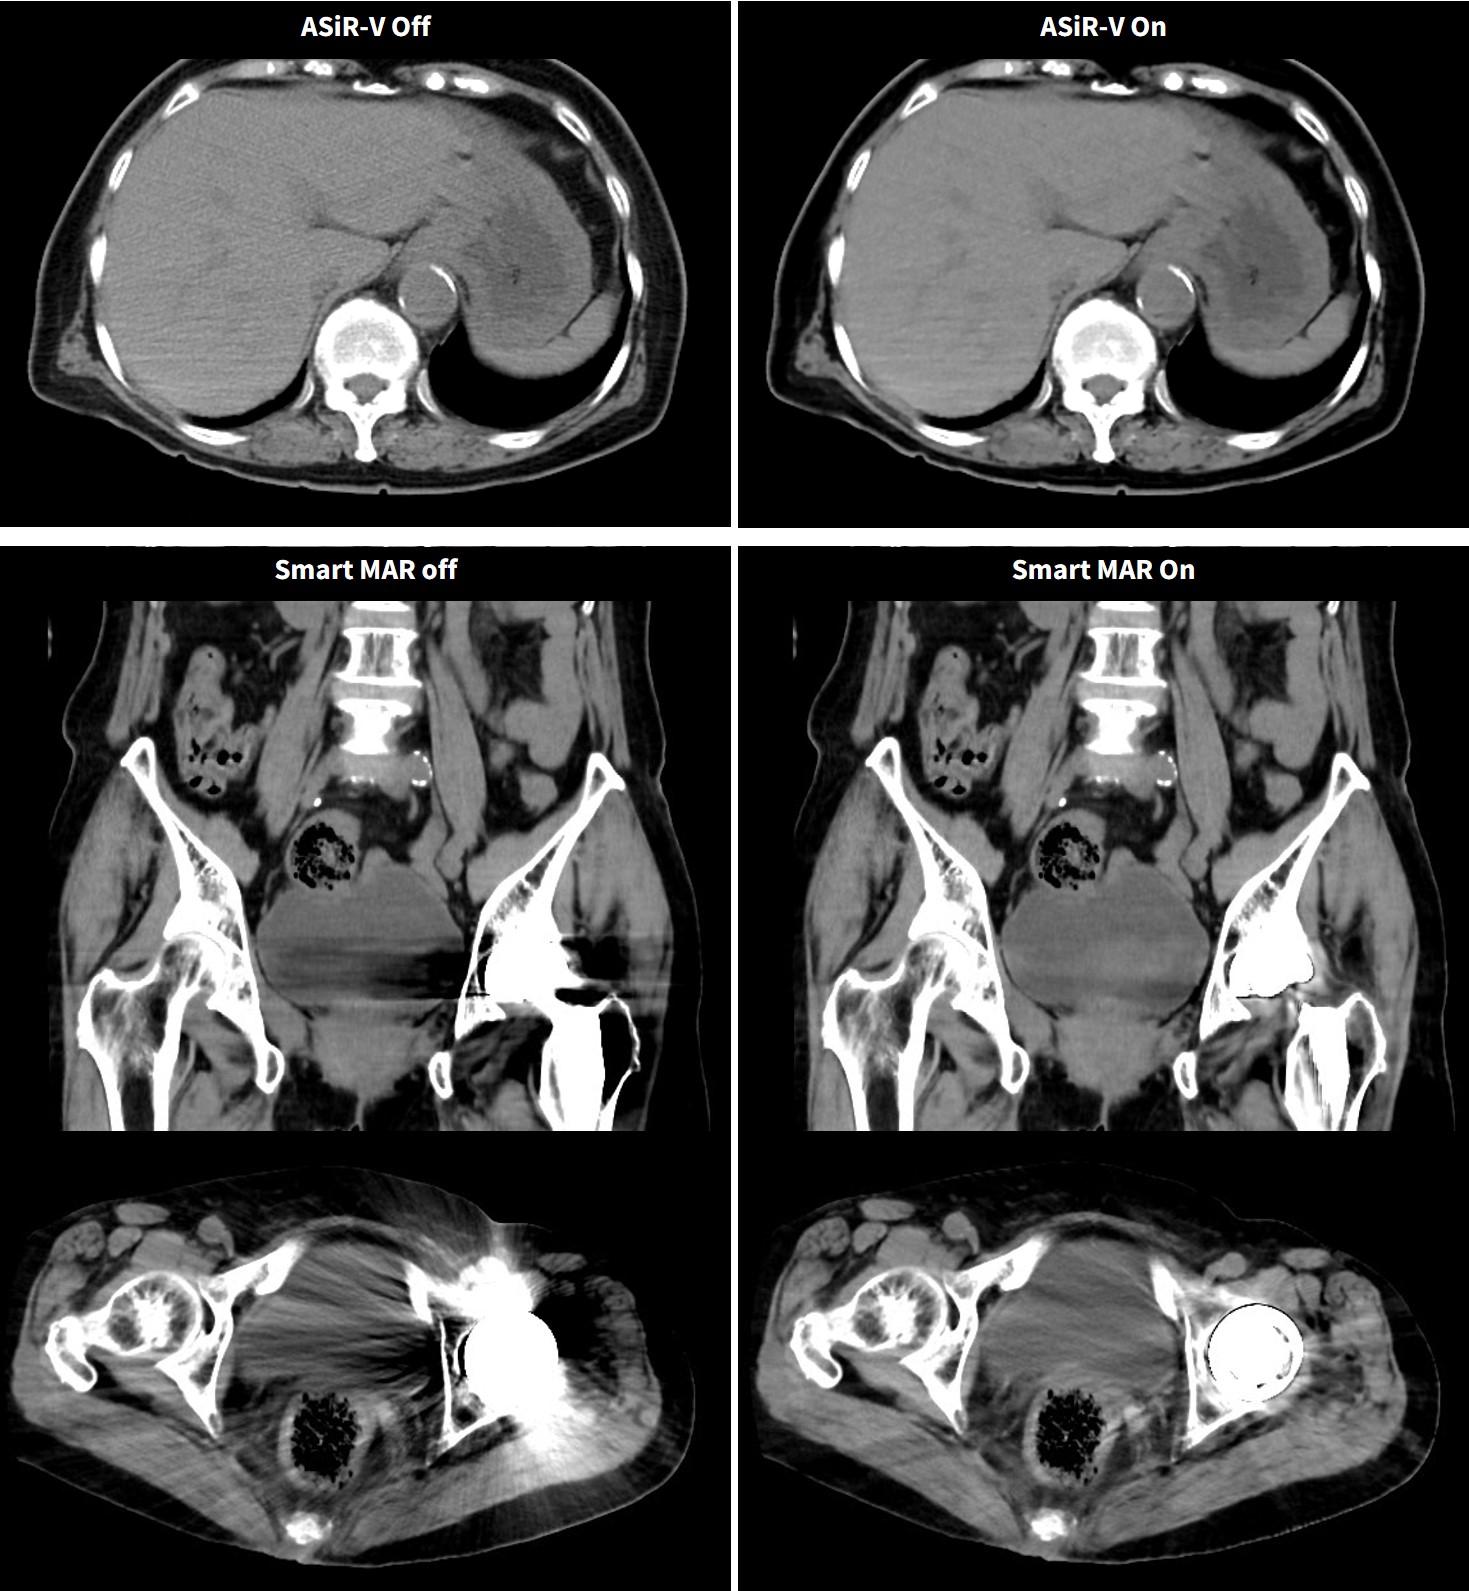

②のmAs不足に対しては、再構成方法のパラメータ調整で調整することも可能である。GEヘルスケア社独自の逐次近似画像構成技術・ASiR-Vは空間分解能を保ちつつ従来比最大91%のノイズ低減が可能である。この技術はmAs不足の場合のノイズリカバリーや低コントラスト分解能向上、被ばく低減などに応用可能である。ASiR-Vではノイズ低減度合いを10-100%で選択可能なので当院ではルーチンでASiR-V30%を使用し、これは1.36倍の線量相当のノイズ低減効果がある。

また、人工骨頭などの高吸収体によるアーチファクトに対しては、Smart MARという金属アーチファクト低減アルゴリズムを適用させることにより補正が可能である。金属インプラントの入っていることの多い高齢患者に対して有効な機能である。